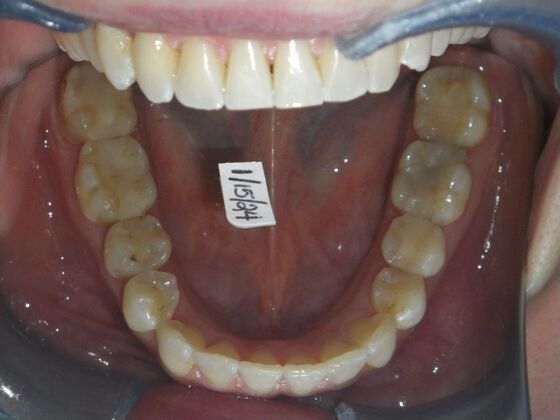

This patient had concerns with the lower anterior teeth. There were some slight rotations and the midline of the lower incisors wasn't lined up with the upper midline. To correct this we used slenderizing of teeth in strategic areas of the lower arch to correct the rotations and line up the midlines. Patient very pleased with the results.